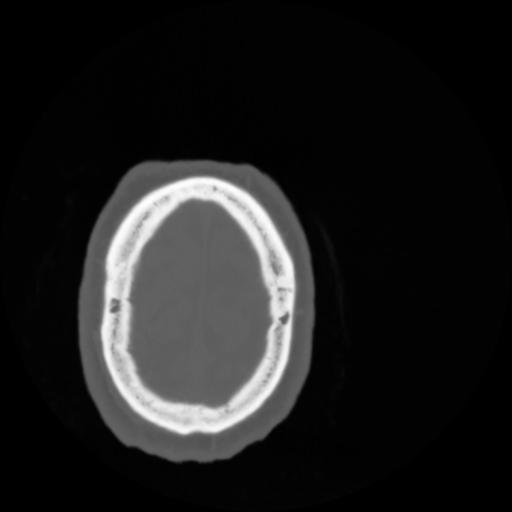

4 CEREBRO,,Vol,0.5,CEREBRO,,